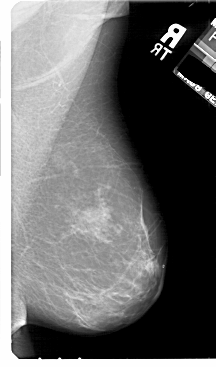

A_1811_1.LEFT_MLO

LEFT_MLO LINES 5491 PIXELS_PER_LINE 3301 BITS_PER_PIXEL 12 RESOLUTION 43.5 OVERLAY

FILE: A_1811_1.LEFT_MLO.OVERLAY

TOTAL_ABNORMALITIES 1

ABNORMALITY 1

LESION_TYPE MASS SHAPE IRREGULAR MARGINS MICROLOBULATED

ASSESSMENT 4

SUBTLETY 2

PATHOLOGY BENIGN